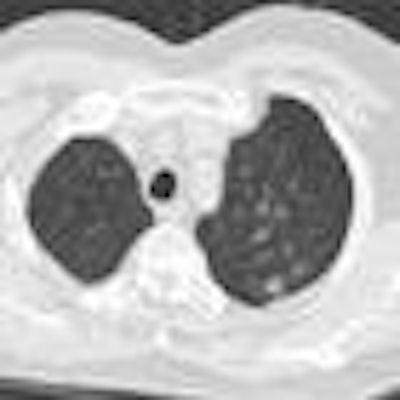

March 8, 2013 -- VIENNA - Visibility is the shield that can protect radiology against the slings and arrows steadily lining up against it, according to experts who spoke at a professional challenges session on Friday at ECR 2013.CAD scheme automatically characterizes lung nodules

March 9, 2013 -- VIENNA - Taking a step beyond lung nodule detection schemes evaluated in previous studies, researchers from the Netherlands have developed an automated method of characterizing nodules as solid, part-solid, or nonsolid, pointing the way to different patient management paths, according to a presentation at ECR 2013.